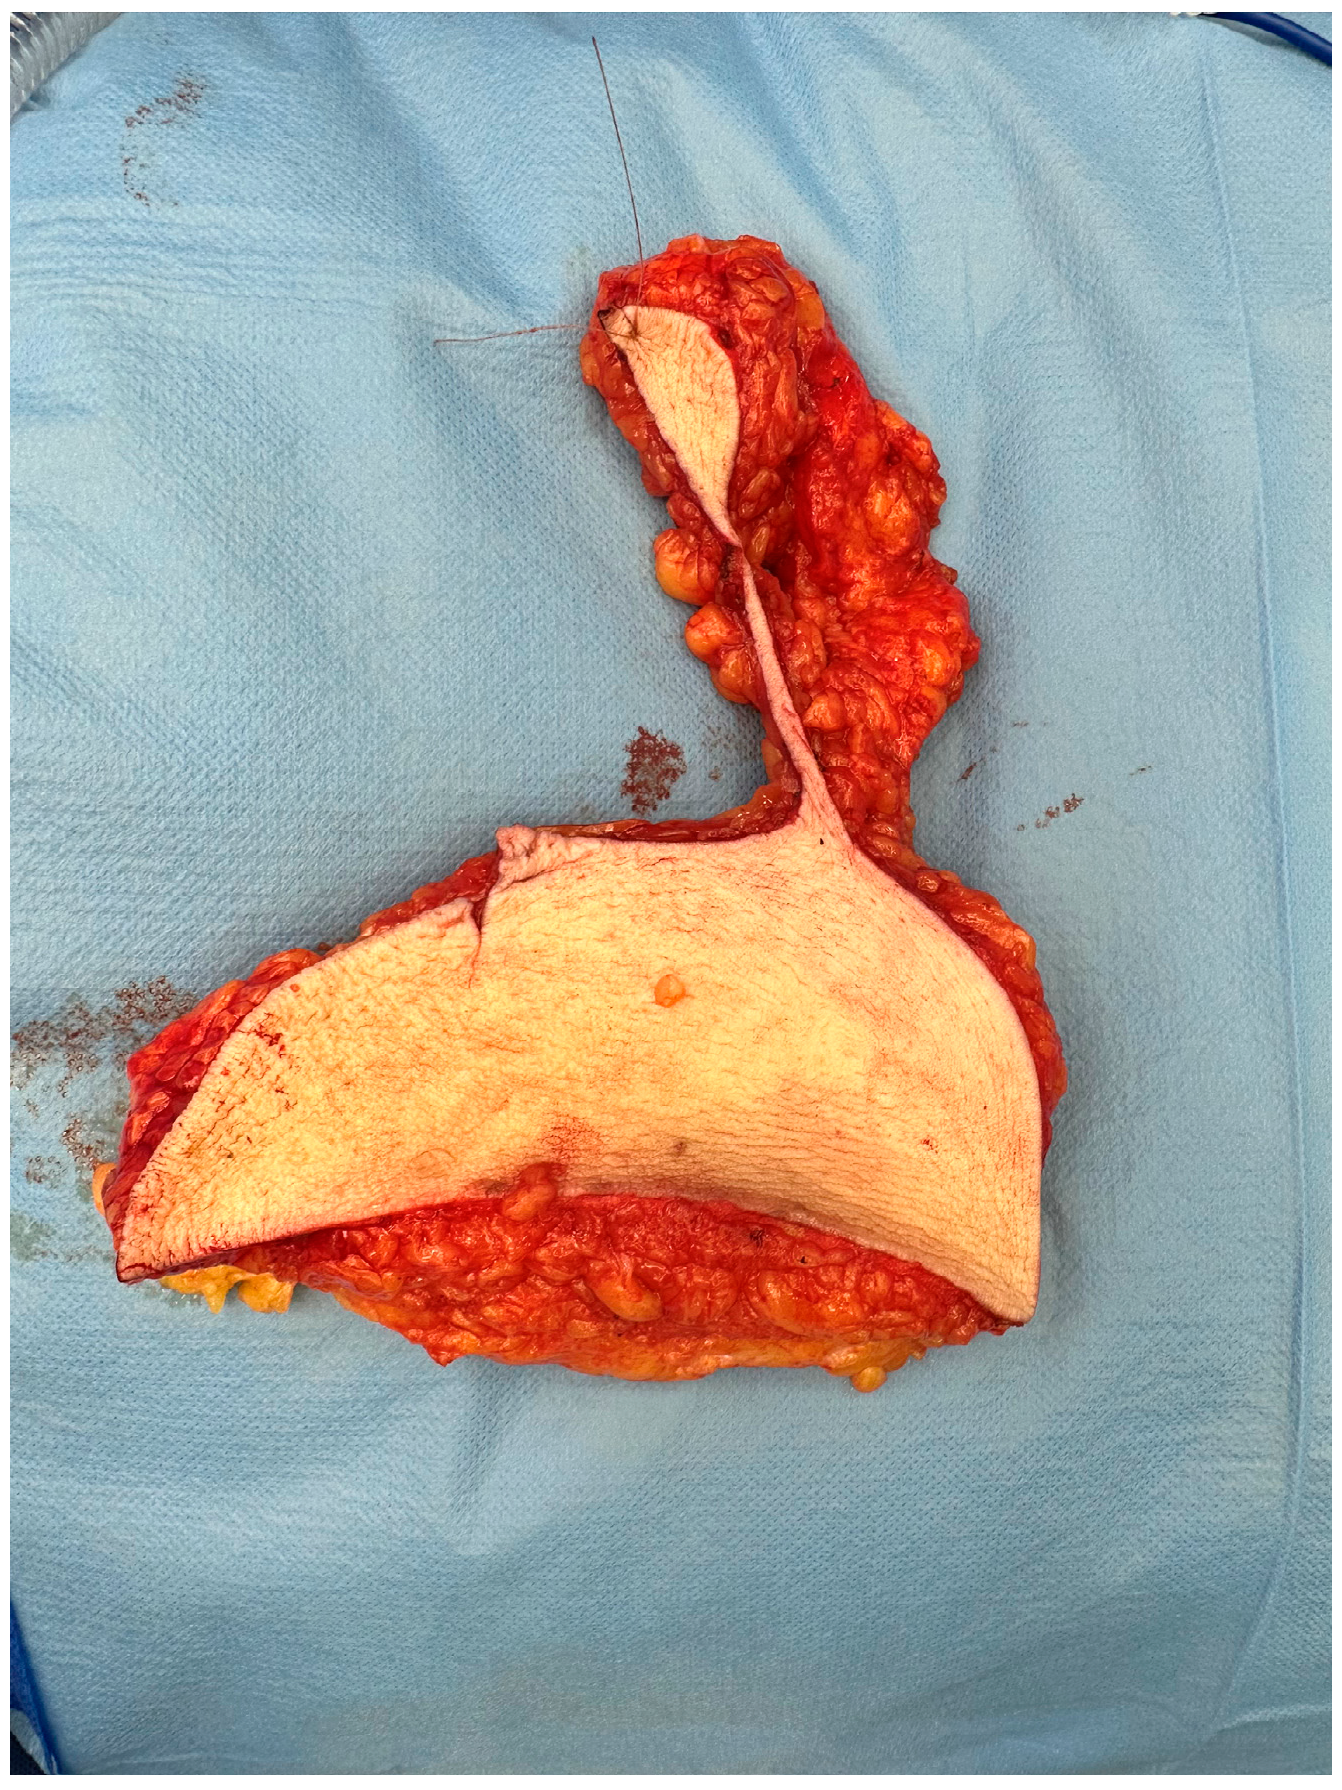

All patients underwent contralateral breast reduction surgery for symmetry using the Wise pattern technique. This is the most common technique used in breast reduction surgery [8]. The surgical protocol was changed on 20 July 2022 as resections were made in toto and marking of the excised tissue was conducted cranially (Figure 1). This consensus started since that date and all the plastic surgeons involved in this procedure followed it accordingly. Before this protocol, the resection of the breast tissue could be conducted in toto or in small pieces, and no marking was requested.

Figure 1.

Reduction specimen marked cranially.